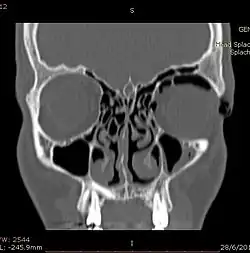

| Woman with preorbital swelling in orbital emphysema shown in CT scans | |

Computed tomography (CT)

Computed tomography is effective and sensitive in the diagnosis of orbital emphysema,[3][37] as it can confirm the anatomical location and size of air, bony defects, indentation of the eyeball, and the condition of the optic nerve, as well as the presence of any extraocular muscle entrapment and herniation of preorbital fat into the sinus cavities.[3][15][38] The location of the orbital emphysema is present near the site of the fracture.[1][3] The scans are usually taken along the transverse plane. Transverse images allow the evaluation of fractures in medial and lateral orbital walls. By reformatting these transverse images or taking coronal images, the examination of orbital floor and roof is permitted. Helical scanning is preferred as it has a lower imaging time and radiation dose comparing to conventional scanning, especially when reforming transverse helical scans into coronal images.[3] The staging of orbital emphysema can then be determined with visual acuity examination and ophthalmoscopy.[6] A disadvantage of using a CT scan is that when detecting air after orbital trauma, the presence of a wooden foreign object can give a false positive result of orbital emphysema. The wooden object can mimic the presence of orbital emphysema. Therefore, patients’ medical history is crucial in making the correct diagnosis.[3]